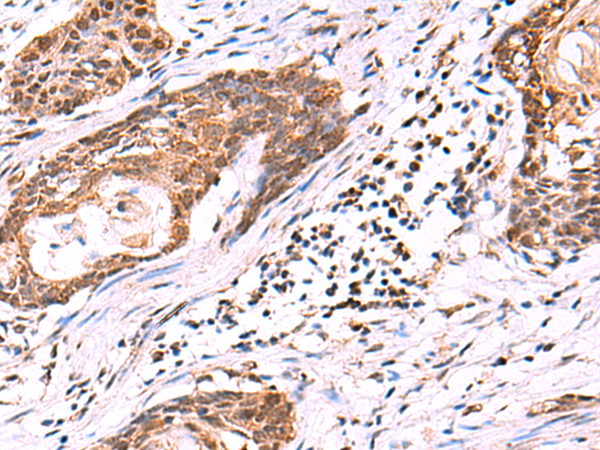

分类: 科研抗体货号: P10203别名: RaLP; SHCD应用: IHC反应种属: Human